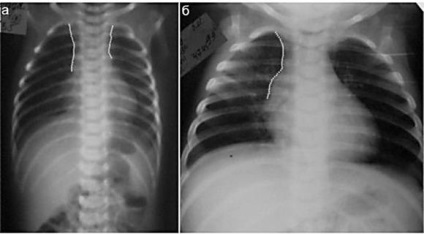

diagnózis thymomegaly

Thymomegaly fejlettségű gyermekek definíciója szerint attribútumok (megjelenés a rák röntgen), és az eredményeket a speciális méréseket.

Minőségi jellemzői diagnosztizálására fokú felbontás thymomegaly thymus árnyéka a röntgenfelvételen. A kezelési rend választjuk szigorúan egyénileg, attól függően, hogy a betegség, az általános állapot, az immunrendszer és a súlyosságát a gyermek életkora.